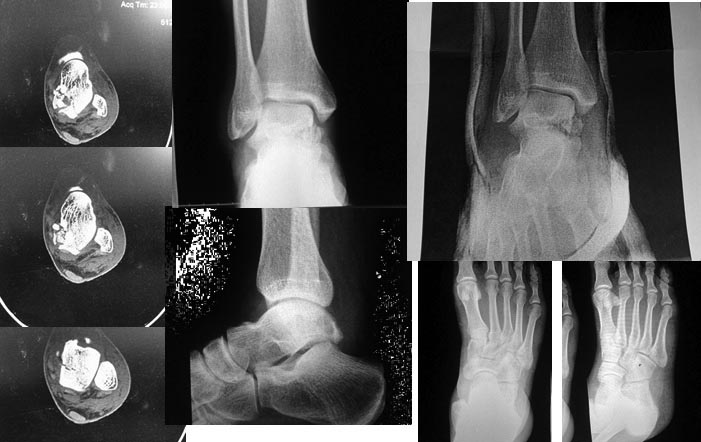

Больной Б., 31 год, мужчина, спортивный парень, занимается спортивным туризмом.Травма неделю назад: на тренировке по скалолазанию упал с высоты около 3-х-3,5 м на маты 30см, неудачно приземлился на носок стопы

(парень имеет достаточную мышечную массу при росте 170 вес около 80кг). Так уж вышло, что я был в соседнем помещении, и меня сразу позвали на помощь. Визуально имелся подвывих стопы кнутри, наружная лодыжка неестественно сильно контурировала, подвывих сразу был устранен, тенденции к повторному вывиху,подвывиху не было, наложена шина. При рентген-диагностике обнаружен перелом таранной кости, выполнена КТ. Выявлено: Оскольчатый перелом таранной кости со смещением в таранно-пяточном сочленением, без смещения в голеностопном суставе. Наложена гипсовая иммобилизация. Неделю получал консервативное лечение, отек умеренный, не напряженный, в большей мере спал, пузырей нет. Сегодня выполнена контрольная рентгенография. Вопросы: Имеется ли импакция костной ткани тарана? Сохраняется подтаранный подвывих? Какой вариант лечения предложили бы вы(консервативный, оперативный)? Если рассматривать возможный вариант оперативного лечения, мое мнение - предпочтительна дистракция и фиксация в полноценном аппарате внешней фиксации. А может быть "не трогать", и лечить консервативно? Буду признателен за советы, парень молодой, необходимо получить хорошую функцию.

Импакция есть однозначно, незначитеьный подвывих имеется. Моё мнение оперировать необходимо, целесообразнее малоинвазивно. С скалолазанием на ближайший год перерыв.

Спасибо за мнение. "целесообразнее малоинвазивно" Как именно? И что конкретно оперировать: устранять возможно имеющийся подвывих и фиксировать(опять как?, трансартикулярно спицами или винтами) Или же помимо этого фиксировать перелом тарана, однако, фрагменты достаточно малы для фиксациии их винтами, только если винтом Герберта. Если оперировать, то самый малоинвазивный способ по-моему - аппарат внешней фиксации.

А почему собственно не аппарат?, если у Вас это хорошо получается. "Минус" - аппарат выключает из работы сустав. Можно скомбинировать, аппарат для репозиции и на короткий срок иммобилизация после фиксации отломков и устранения подвывиха, после фиксации отломков, в т.ч. и винтами твин-фикс.